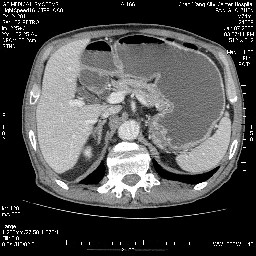

女,74岁,呕吐10余日

病变主要位于钩突(癌)。如是壶腹部,肝内外胆管扩张明显。

十二指肠降段扩张,水平段狭窄成鼠尾状,肠壁明显增厚,胰腺勾突增大成不均匀强化,其内可见低密度区,胆囊增大,1十二指肠水平段腺癌侵犯胰腺勾突可能大,2胰腺癌侵犯十二指肠(只有胆囊增大没有肝内外胆管扩张不好解释)代除外.

支持壶腹mt侵及胰腺,那个椎体是骨疝吗???

十二指肠降段扩张,水平段狭窄成鼠尾状,肠壁明显增厚,胰腺勾突增大成不均匀强化,其内可见低密度区,胆囊增大,1十二指肠水平段腺癌侵犯胰腺勾突可能大,2胰腺癌侵犯十二指肠 。

今日手术结果:胰腺钩突癌侵犯十二直肠,腹腔淋巴结转移.